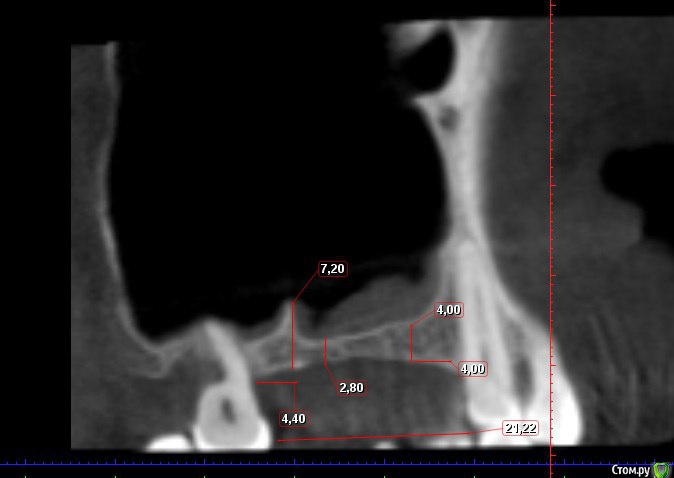

Kovalov Igor Опубликовано 19 мая, 2016 Поделиться Опубликовано 19 мая, 2016 (изменено) Здравствуйте уважаемые форумчане! Нужен совет по повторному синуслифтингу....3 месяца назад проводилась попытка синуслифтинга в 1 сегменте, отсутствие 14,15,16 зубов ... Разрез, формирование окна, в этом случае выбрал вход в синус с двух окон в проекции 14 и 16, получить перфу возле септы в области 16 когда отслаивал ... 14 отслойка без проблем... закрыл окна мембраной и ушил отправил погулять на 2,5-3 месяца.Вопрос как поступить ? Сделать одно большое окно? Как быть со спайками и как сложно их отделять ? Мембрану под перфу не подложил так как не делал ниразу этого... Кт после 3х месяцев ... Изменено 19 мая, 2016 пользователем Kovalov Igor Ссылка на комментарий

kriokov Опубликовано 19 мая, 2016 Поделиться Опубликовано 19 мая, 2016 пошел бы стандартно одним окном, да и первый раз думаю надо было одним окном идти, там не полная септа.Иногда приходиться остро работать на спайках как при расщеплении. Не знаю, но мне здесь одно здоровое окно видиться. И наверное зря Вы септу не спилили или не выкусили при первом заходе, если решили через три мес на повторный идти. Синус не плохо выглядит, думаю нормально все будет. 6 Ссылка на комментарий

Kovalov Igor Опубликовано 19 мая, 2016 Автор Поделиться Опубликовано 19 мая, 2016 пошел бы стандартно одним окном, да и первый раз думаю надо было одним окном идти, там не полная септа.Иногда приходиться остро работать на спайках как при расщеплении. Не знаю, но мне здесь одно здоровое окно видиться. И наверное зря Вы септу не спилили или не выкусили при первом заходе, если решили через три мес на повторный идти. Синус не плохо выглядит, думаю нормально все будет.спасибо за ответ... думаю из-за плохого обзора и малого окна 6-7 мм в диаметре и случилась перфа, септу забыл спилить, все было как в тумане))) учту этот нюанс ))) Ссылка на комментарий

red_butler Опубликовано 21 мая, 2016 Поделиться Опубликовано 21 мая, 2016 Куда вы 2гр L сыпите та? Тромбуете штоль?Даже еще раз пересмотрел срезы, Вы считаете что на такой операционной площади и при таком строении синуса расход будет меньше? 3 Ссылка на комментарий

Kovalov Igor Опубликовано 21 мая, 2016 Автор Поделиться Опубликовано 21 мая, 2016 Даже еще раз пересмотрел срезы, Вы считаете что на такой операционной площади и при таком строении синуса расход будет меньше?Ушло 2 грамма вы правы! ))) Спасибо всем за советы , ошибки были в первом случае малое и высоко расположенное окно, сделал в этот раз одно большое окно, спайки были только по периметру окна , было ощущение что окно начало заростать костью через три месяца, будто пластинка была поверх мембраны , может показалось ...Отслаивал до септы, графт 1,5 гр. в синус и 0,5 латерально от винтов и укрыл мембраной 25*25 владмива, мембрана не понравилась если честно ) Ссылка на комментарий